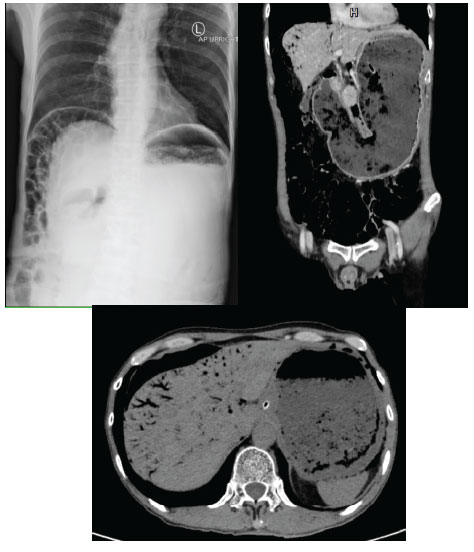

A 55-year-old man presented to an emergency department with a history of abdominal pain and vomiting for one week. He had a history of having peptic ulcer perforation surgery. He appeared weak and frustration from pain, abdominal distension at upper abdomen without peritonitis sign on physical examination. Initial abdominal radiograph revealed pneumoperitoneum under both hemidiaphragms with markedly distension of stomach containing food content. Further computed tomography demonstrated evidence of gastric outlet obstruction without intra or extraluminal mass. There is also massive amount of portal venous gas in both lobes of liver. After patient resuscitation with intravenous fluid and nasogastric intubation for gastric decompression, his condition returned to normal, with no sign of peritonitis nor sepsis. Therefore, the upper gastrointestinal endoscopy showed gastric outlet obstruction from chronic peptic ulcers. The endoscopic balloon dilatation of the obstruction part was successful, and he was discharged home with full recovery in one week.

Figure 1: Imaging of patient.